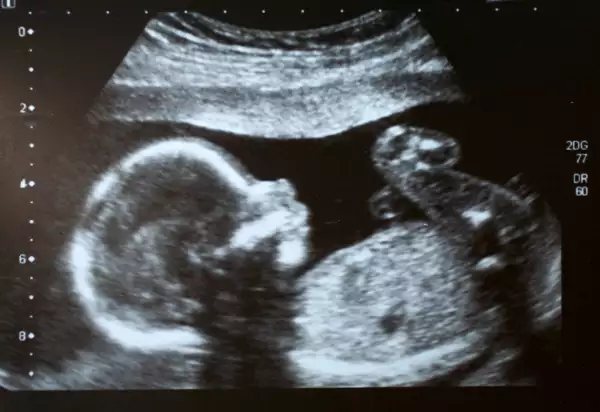

Todos los alimentos que se ingieren durante el embarazo, están formando los órganos y los tejidos del bebé. Es por eso, que es fundamental que lleves una alimentación variada, adecuada, completa y suficiente en este periodo de formación.

Andrea Alverde explica que en cada trimestre del embarazo, se van a desarrollar órganos y tejidos específicos por lo que la alimentación durante esas 40 semanas va a cambiar constantemente para que el crecimiento y desarrollo sea de la mejor manera.